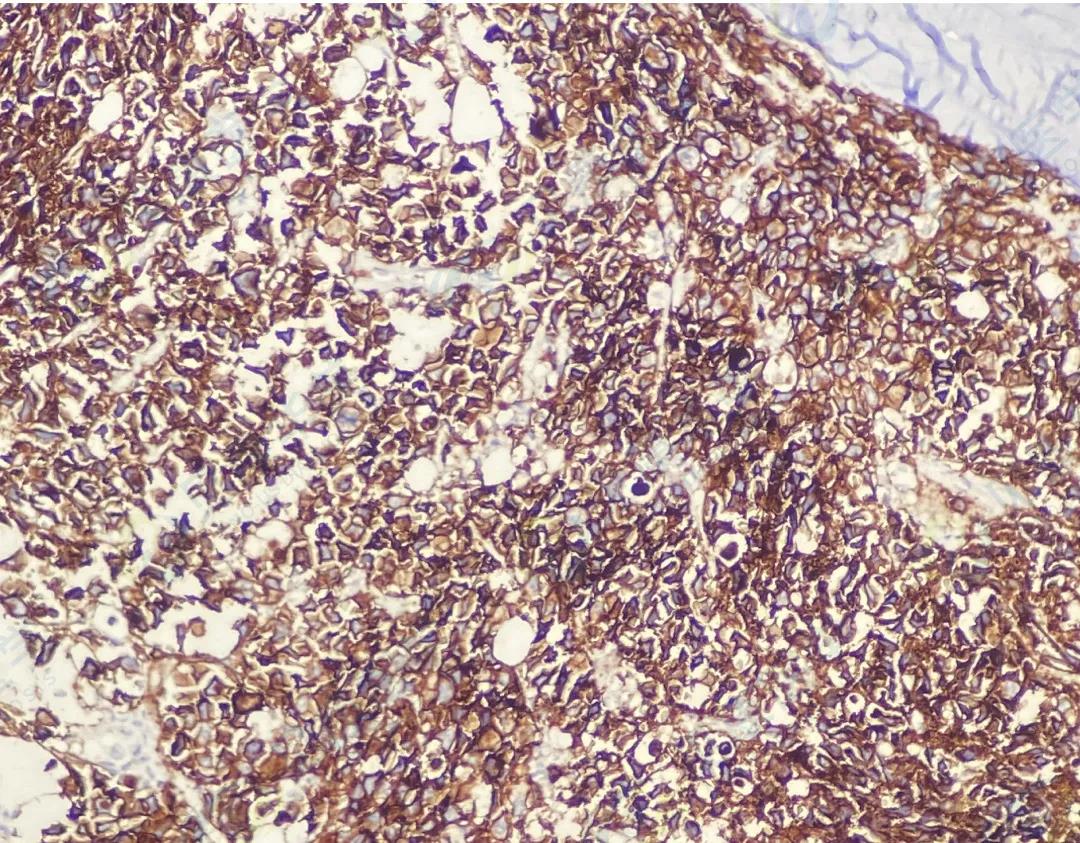

CD138

CD38